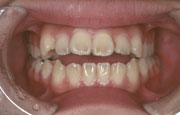

矯正の症例

| 【Before】 | 【After】 | |